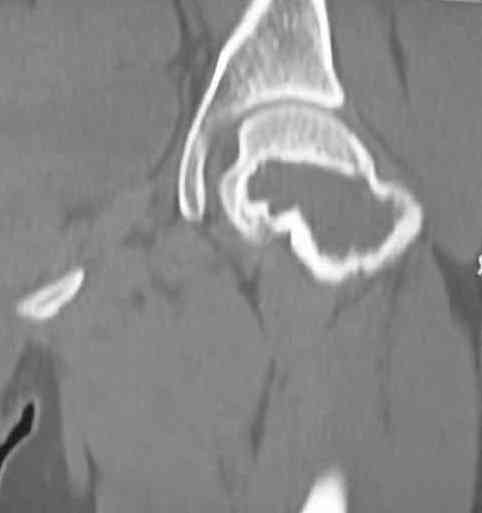

Больная Л., 23 года.

Из анамнеза:со слов больной в 2006 г. появились боли правой н/конечности, обратилась поместу жительства к хирургу, было выполнена МРТ поясничного отдела позвоночника,назначено физиолечение.

Через 2 месяца боли прекратились, через 4 месяца рецидив болевого синдрома. С 2006 – 2010 проводилось консервативное лечение по поводу остеохондроза поясничного отдела позвоночника. В октябре 2010 г. боли усилились. Выполнены Ro и КТ правого тазобедренного сустава, выявлен очаг патологической перестройки. Была направлена на консультацию в УНИИТО.

В УНИИТО виюне 2011 г. поставлен дифференциальный диагноз между фибромой, солитарной костнойкистой и гигантоклеточной опухолью.